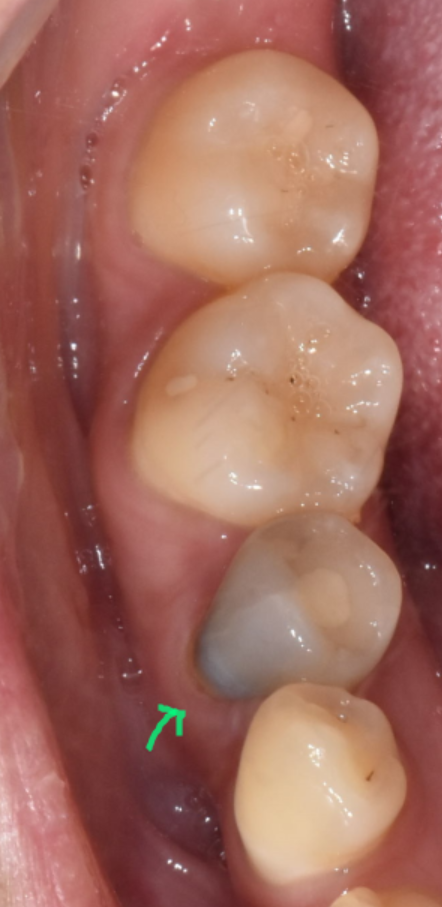

240312 뿌리 끝 염증

오늘 환자분처럼 신경치료 후 보철을 씌워주지 않으면

치아가 약해지면서

다양한 문제가 생길 수 있어요.